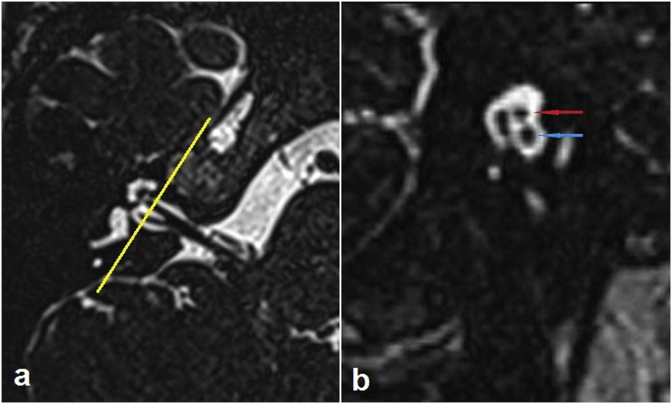

Fig. 2.

Three dimensional constructive interference in steady state (3D-CISS) images of the normal-hearing right ear of a 40-year-old woman. (a) Axial section at the level of the inner acoustic canal. The yellow line which is drawn perpendicular to the course of the inner acoustic canal represents the plane in which the parasagittal oblique image is created. (b) Parasagittal oblique section created with the use of multiplanar reformation tools. The red and blue arrows show the facial and cochlear nerves, respectively.